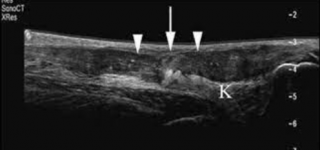

Способы диагностики

При внешнем осмотре врач не сможет точно определить степень тяжести и вид травмы, так как при повреждении голеностопа их симптоматика схожа. Осуществляется дифференциальная диагностика для исключения переломов костей, вывиха, разрыва ахиллова сухожилия. Обязательно пациент проходит рентгенографию, с помощью которой можно обнаружить трещины и разломы в костных структурах. УЗИ, КТ и МРТ – более информативные методы обследования, позволяющие установить любые патологии в соединительных тканях и мышечно-связочном аппарате.

Инструментальная диагностика необходима для выявления воспаления, которое развивается после травм. Дополнительно пострадавший сдаёт общие анализы крови и мочи, по результатам которых можно оценить общее состояние организма.